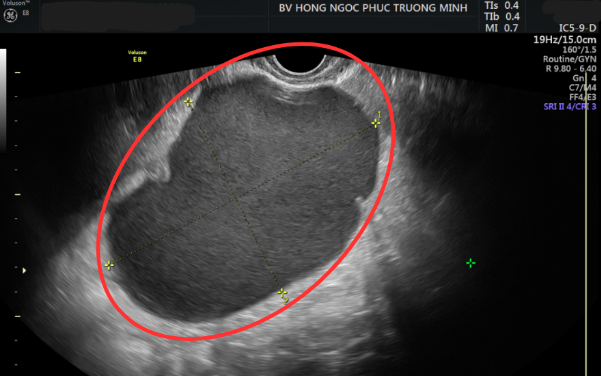

Sau khi thăm khám và siêu âm, bác sĩ phát hiện chị H có một khối u kích thước 10x13cm ở buồng trứng phải, nghi ngờ bên trong có nhiều máu đông, dấu hiệu điển hình của u nang socola, có nguy cơ ảnh hưởng tới sức khỏe và khả năng sinh sản.

Kết quả thăm khám và siêu âm cho thấy khối u nang lớn có kích thước lên tới 10x13cm.